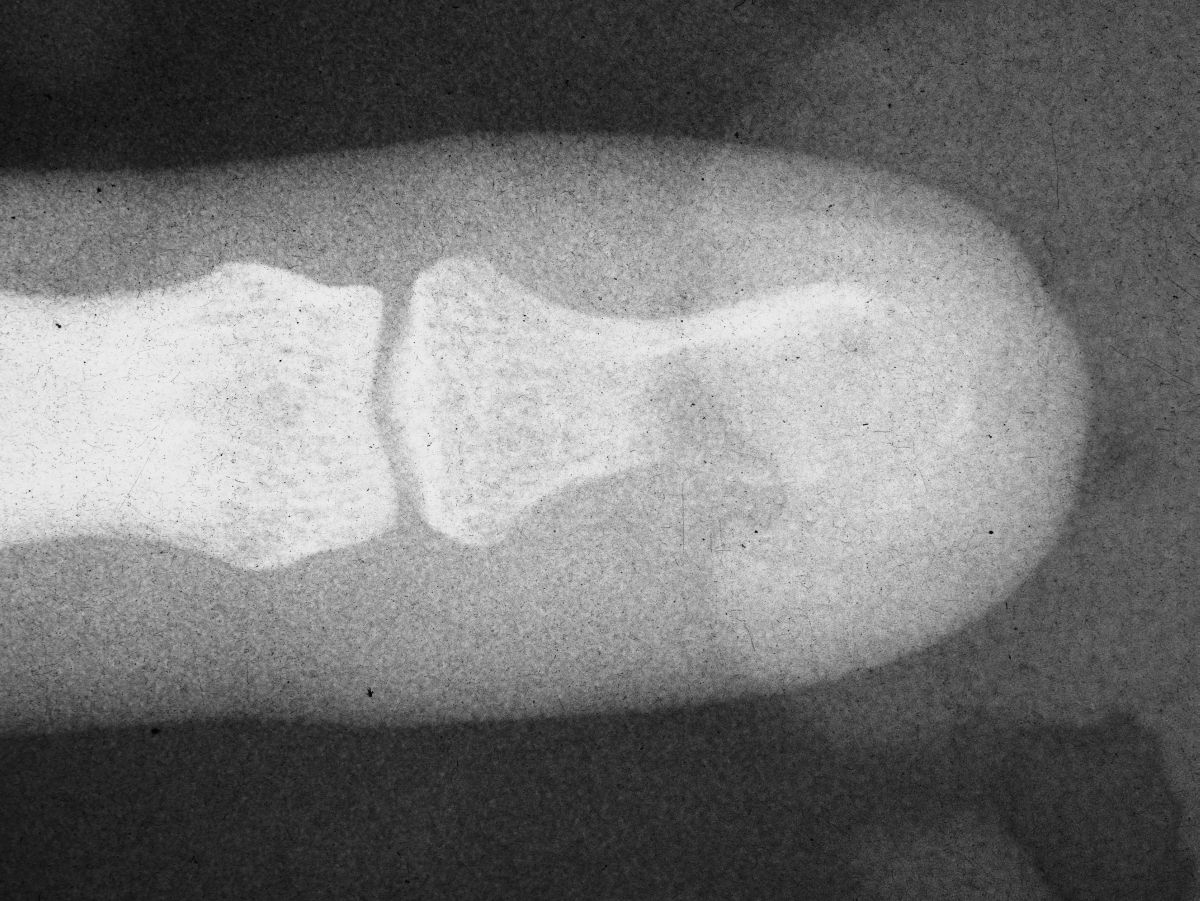

| Case 1. This patient presented with a progressive index finger nail deformity years after an open crush injury of that fingertip. |

| Xrays show loss of much of the distal half of the distal phalanx, with cortical disruption. |